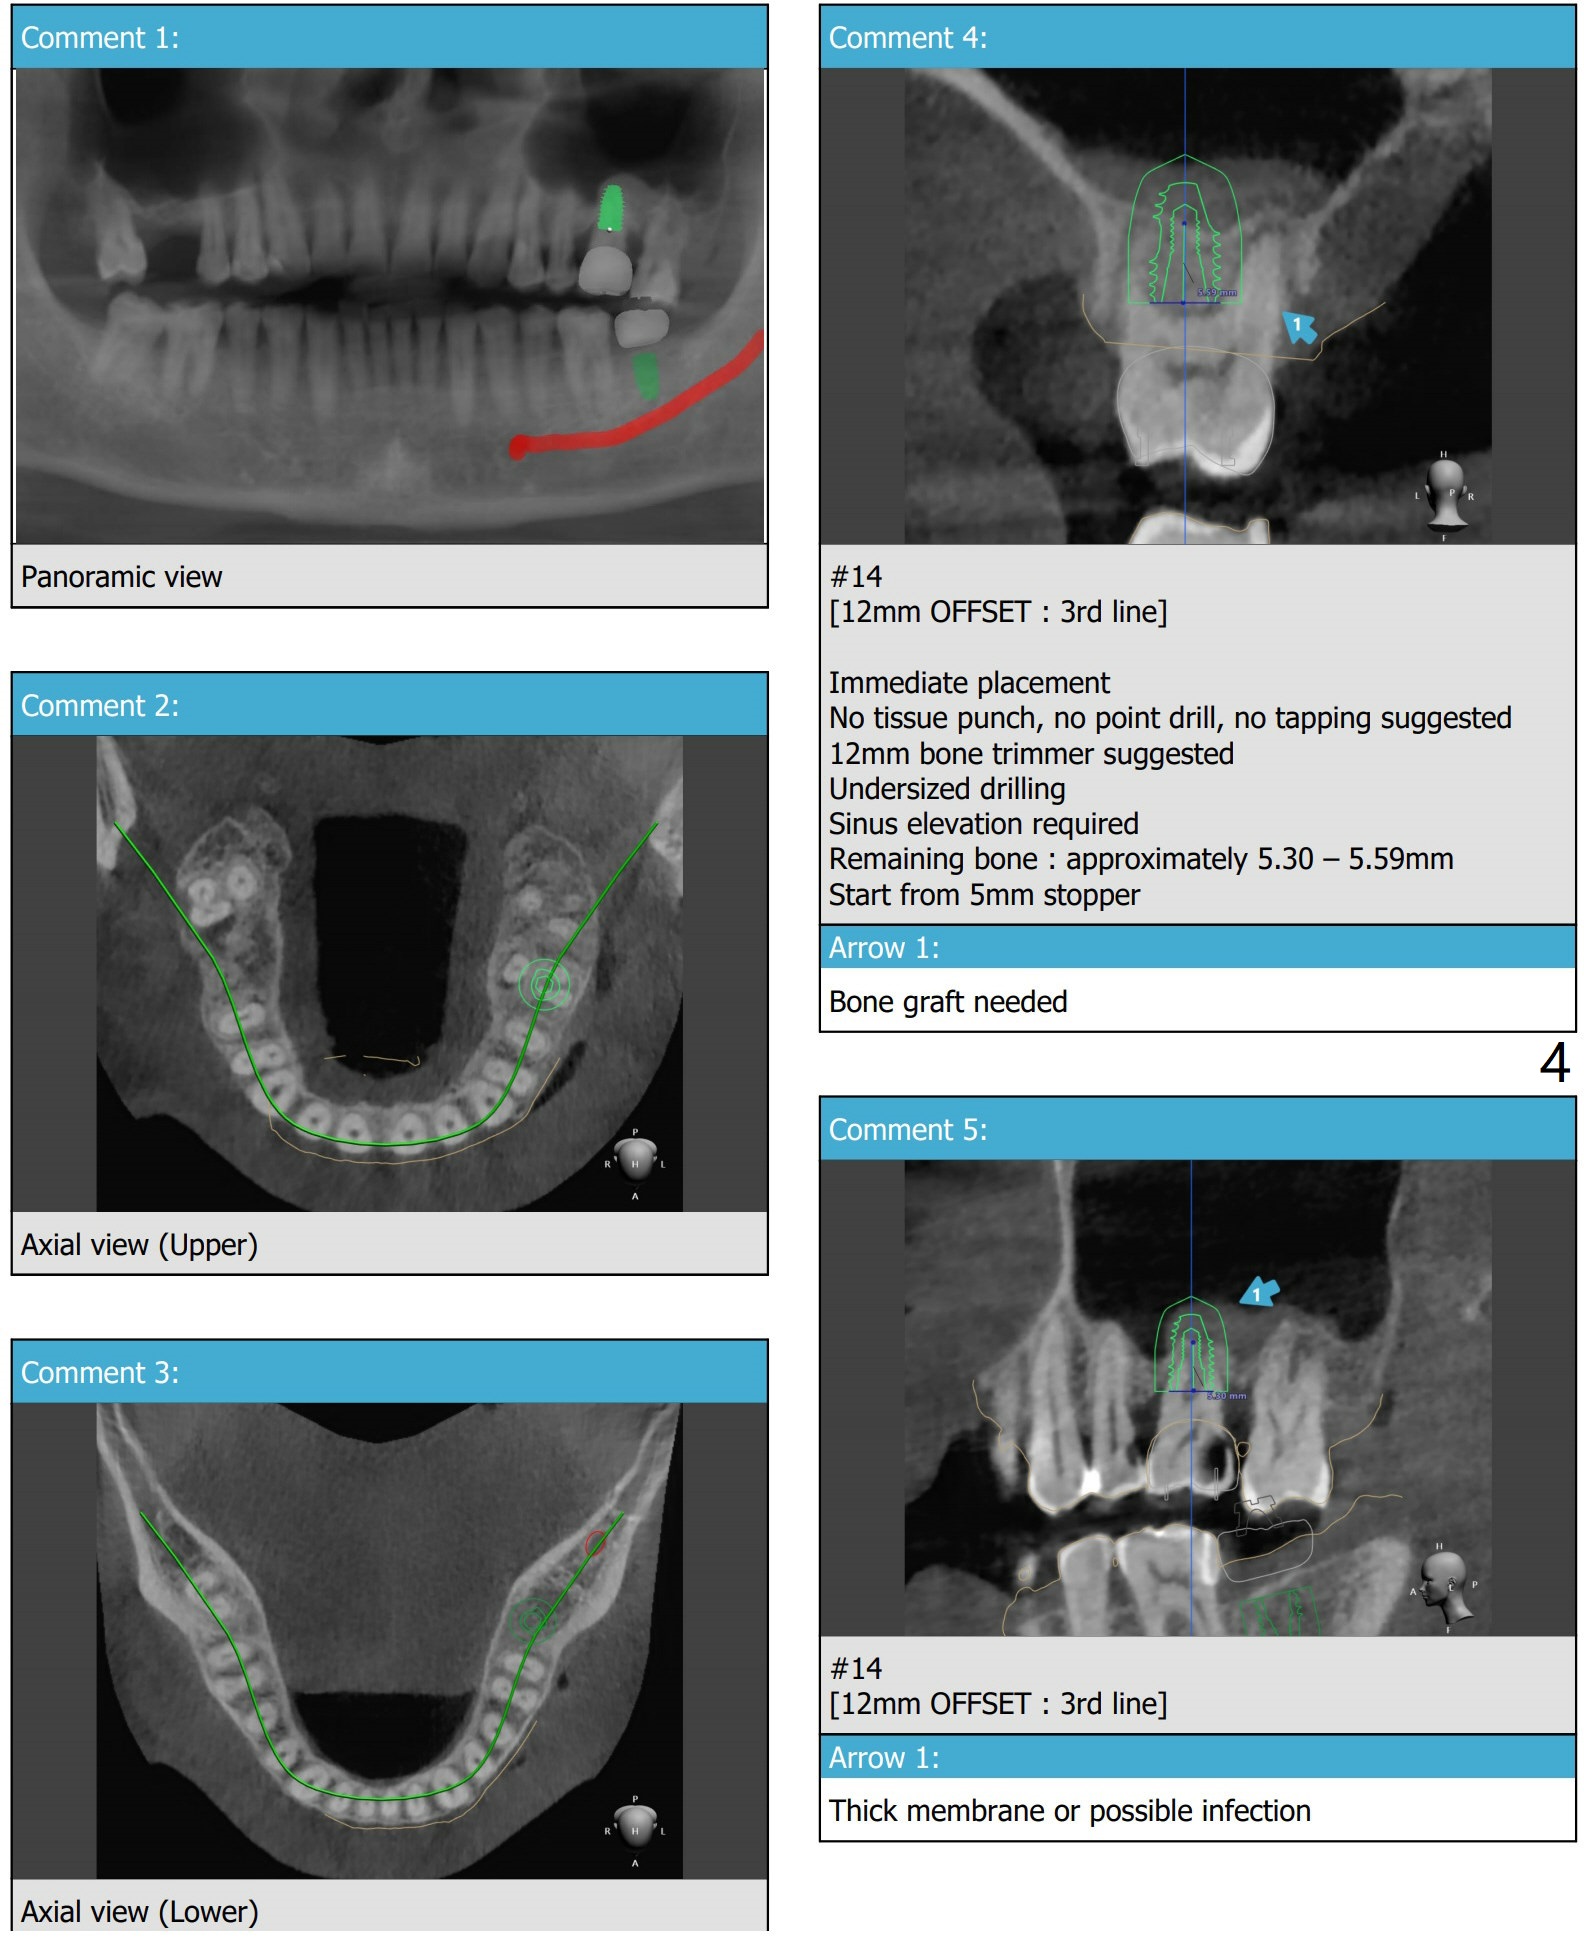

Short Implants

PRFx1 (18 14)

Return to Prevent Molar Periimplantitis (Protocols, Table) No Caries Metronidazole  第二磨牙即种